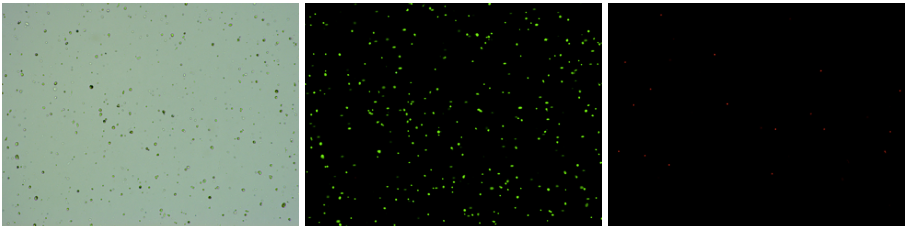

人腎癌樣本,細胞活率:94.69%,結團率:6.6%